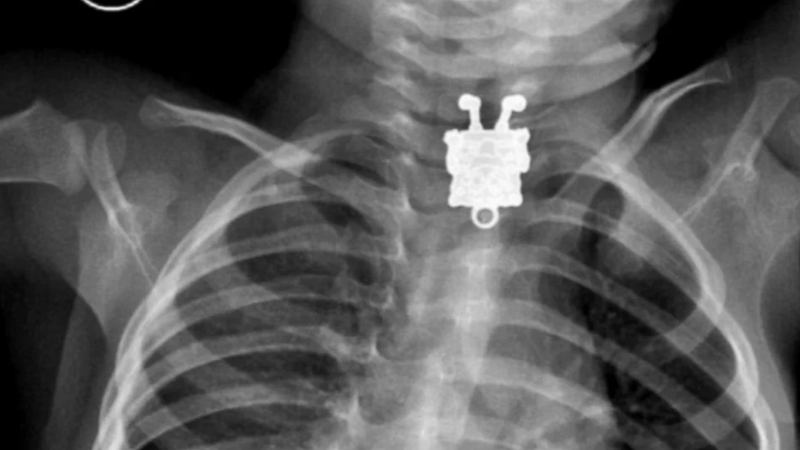

11. Рентгенівський знімок 16-місячної дитини, що проковтнула брелок